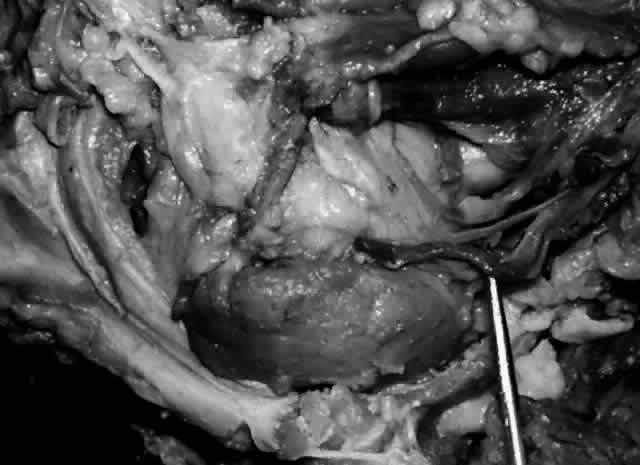

The parenchyma of the gland is made up of small lobules separated by a fine connective tissue network. The lacrimal gland has approximately 12 secretory ducts (Fig. 7), which average 0.66 mm in diameter and 2.31 mm in length.4 Two to five of them originate from the orbital lobe and six to eight from the palpebral lobe. The ductules from the orbital portion of the lacrimal gland pass through the parenchyma of the palpebral lobe before exiting into the superotemporal portion of the conjunctival fornix 4 or 5 mm above the upper border of the tarsus. One or two may open near the lateral canthus.5 Excision of the palpebral lobe may therefore interrupt drainage from the orbital lobe as well.

Fig. 7. Secretory ducts (arrow 1) of the right lacrimal gland (arrow 2) are seen passing to the palpebral conjunctiva (arrow 3). (Courtesy of James Sanderson, MD, Orkan Stasior, MD, and George Stasior, MD)